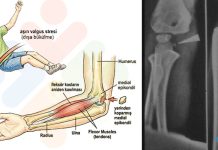

Proximal Humerus:

Humerus başında tuberkulum majus palpe edildikten sonra 2 cm distalindeki noktaya uygulama yapılır.